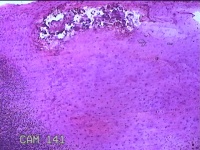

右侧食指远端结节

性别

男

年龄

47岁

临床诊断

皮下结节

一般病史

发现右侧食指3天。

标本名称

大体所见

灰白暗红色带皮肤样结节1.2x0.7x0.3cm一个,表面糜烂,切面灰白粉红色,质中。